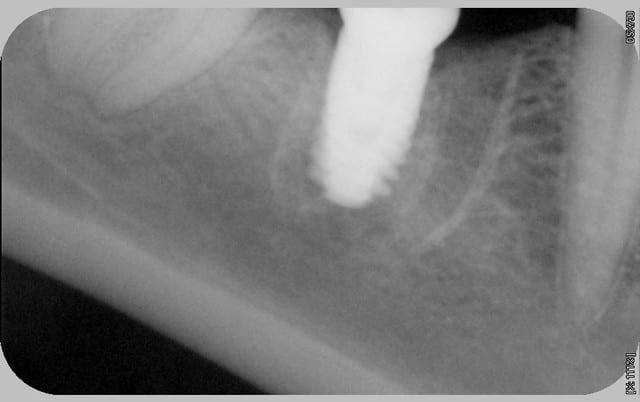

tous mes implants sont ostéo-intégrés, mais je trouve que la cratérisation est très importante et surtout très rapide.

donc pour moi, il y a un problème même si le taux de succès est de 100% en 2 ans.

Il manque les radios du jour de la pose, j'ai l'impression que les implants ne sont pas assez enfouis . Pa exemple Anthogyr recommande de poser l'Axiom 0.5mm en sous crestal, que préconise Tekka ?

En ce qui concerne la radio de la 21 , on dirait qu'il a été mis dans un site d'extraction et qu'il n'est pas assez large.

voici les radios le jour de la pose

le krestal doit être en crestal et non en infra-osseux: il s'agit d'une connectique à plat et non d'un cône morse.

Mais je penses sérieusement que le problème vient de la connectique qui n'est pas adapté à une position juxta-crestale.

Suffit de voir si quelqu'un a eu les mêmes problème avec l'in-kone et on sera fixé, vu que c'est le même implant, y a que la connectique qui change.